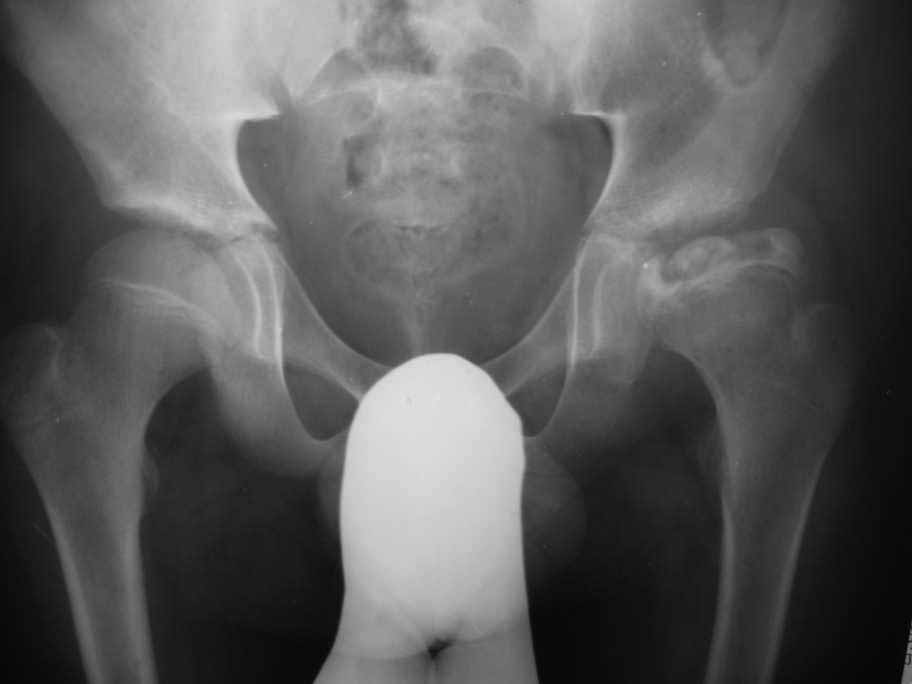

Здравствуйте уважаемые коллеги,Посоветуйте, пожалуйста, тактику лечения для пациента с болезнью Пертеса.

Мальчик 14- ти лет обратился с жалобами на боли в левом тазобедренном суставе. Болеет около шести месяцев

Клинически : Движения в суставе ограничены ,сгибание 90 гр, отведение -30гр,ротационные движения 5-0-5 гр.Спасибо Ihor

1) А точно 14 лет? (Y образный, малый вертел открыты), или эндокринопатия, или...

2) Болеет наверное более 6 мес

3) без проекции по Лаунштейну трудно советовать тактику лечения

4)необходимы снимки в положении отведения бедра (максимально возможного при нулевой ротации)для определения возможных вариантов: а)тройная остеотомия таза (по Соколовскому, Ganz не подходит Y- открыт) + resection osteochondroplasty (хейлотомия) или б) тройная таза

+ вальгизирующая бедра

Уважаемый Ihor! Если внимательно присмотреться на ацетабулярный край ( место прикрепления губы) слева, то вы увидите результат конфликта инконгруэнтности (hinge abduction- шарнирное отведение), при отведении больше 15-20 градусов часть головки, в буквальном смысле, упирается в край впадины и дальнейшее отведение происходит уже с центром ротации в этой точке ( именно поэтому шарнирное отведение). Представим, что тройной остеотомией таза мы "горизонтализируя" , "перекрывая" (изв. за слэнг) головку на 15 град. вызовем конфликт уже при отведении 0-5 градусов.Надежды на ремоделяцию в 14 лет ничтожны.

Эта проблема решается или вальгизирующей остеотомией (дополнительный доступ) или resection osteochondroplasty после капсулотомии при выполнении тройной остеотомии таза. Дислокация бедра по Ганцу (Бернская) Ganz Bernese hip dislocation может быть как этап подготовки к реориентации впадины тройной остеотомией таза (Acetabular Osteochondroplasty and Simultaneous Reorientation: Background and Validation of Concept by Lucas A. Anderson, PA-C; Carmen D. Crofoot, MD; Jill Erickson, PA-C; David A. Morton, PhD; Christopher L. Peters, MD), но не думаю что в этом случае надо вмешиваться на впадине. По поводу ШДУ : справа и больше слева снимок выполнен с наружной ротацией бедра (малый вертел "торчит")поэтому вальга проекционная.